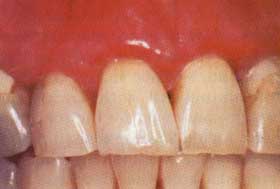

Figure 8a. Atrophic gingival lichen planus in a 56-year-old female. Erythema of the attached gingiva, especially along the free gingival margin. Figure 8b. Custom steroid carrier.

Figure 8c. Partial resolution of the gingiva after four weeks of nightly topical steroid applications in the custom carrier. Note the overall improvement in gingival tone and the "breaking up" of the erythema of the free gingival margin.

Oral lichen planus is often identified by the presence of fine reticular white lines (striae of Wickham) on the lateral borders of the tongue, buccal mucosa, and gingiva (Figure 6). However, striae are not always present, especially in the ulcerative form of the disease; therefore, definitive diagnosis is made by biopsy. Although prospective studies have failed to demonstrate that lichen planus is a premalignant disorder, it is recommended that all patients exhibiting this condition intraorally, particularly those who have had the ulcerative form, receive long-term follow-up (Figure 7).26-28

Occlusive steroid therapy using custom-made flexible mouth guards to localize fluocinonide gel is extremely effective in controlling the gingival lesions of lichen planus.32-33 Fluocinonide 0.05 percent gel is applied to the mouth guards, and patients are instructed to wear them for 30 minutes per application. Therapy can be instituted with a regimen of four applications daily, preferably after meals and at bedtime. The frequency of daily use depends on the response of the lesions. Long-term control of persistent lesions can often be achieved with a 30-minute application every other evening.